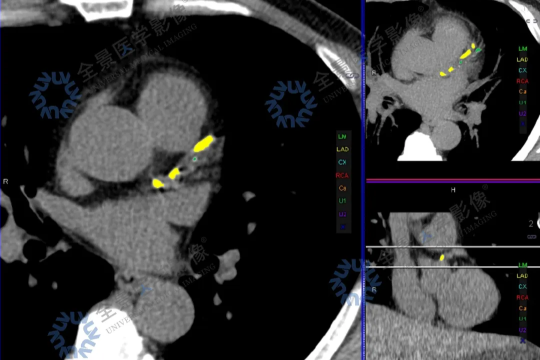

注重技术创新,樊济海带领团队陆续开展了复杂冠心病介入术,心脏再同步化治疗(CRT/CRT-D),左束支区域起搏器植入术,房颤脉冲电场消融(PFA)+左心耳封堵术,室上性心动过速/室性心动过速射频消融术,先天性心脏病介入术,无导线起搏器植入术等先进技术。其中,房颤脉冲电场消融术(PFA)、冲击波球囊等多项技术为区域首例;2024 年完成介入治疗近千例,显著提升医院技术影响力,心血管内科获批「吴江区重点专科」。

心内科积极与上海瑞金医院、中山医院等知名机构合作,共同开创 房颤中心、胸痛中心;牵头创立 樊济海劳模工匠创新工作室,对疑难心血管疾病进行精准治疗,开展突破性的房颤 PFA+左心耳封堵术,房颤 PFA+室上速消融术,房颤 PFA+房扑消融术等联合术式,展现了技术的先进性和团队的卓越能力,进一步提升医疗质量和效率,推动医院成为区域标杆。